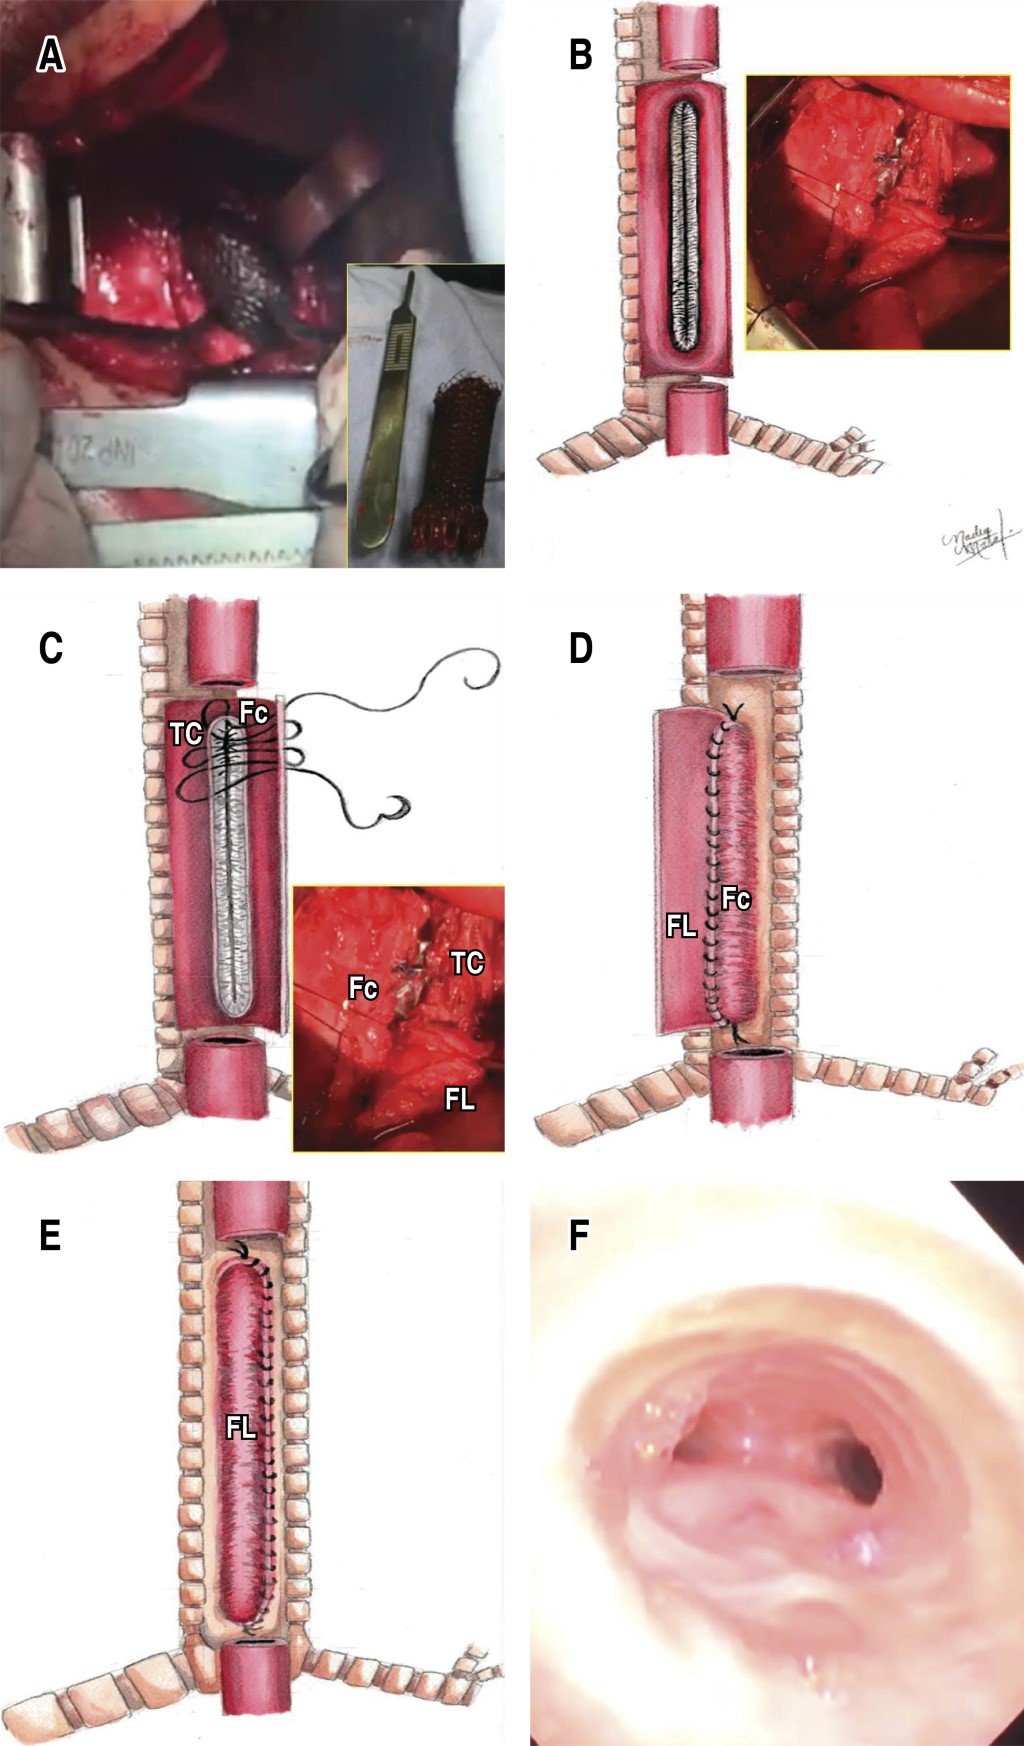

With initial endotracheal intubation guided by bronchoscopy 1 cm below the subglottis, right lateral posterior thoracotomy is performed and esophagus with intense inflammatory reaction is identified, longitudinal esophagotomy is performed, intraesophageal stent is observed, which is removed by fragments with difficulty due to the presence of firm adhesions to the posterior part of the trachea. Once the stent is completely removed, the endotracheal tube is advanced up to 1 cm above the carina, the patient is ventilated with an insufflated balloon and a tracheoesophageal fistula is observed in the membranous portion of the trachea, 10 cm long, the insufflated balloon of the endotracheal cannula allows occluding the air leak and allows distal mechanical ventilation. The edges of the residual esophagus and the excluded membranous trachea are revitalized, the anterior cartilaginous trachea is preserved, esophageal mucosa is removed and the membranous tracheoplasty is performed with two esophageal flaps, A short flap with mucosectomy as the first plane of membranous tracheoplasty anastomosed to the cartilaginous edge of the trachea and a subsequent long esophageal flap covering in a second plane the totality of the neotrachea with simple stitches with 3-0 vicryl. Hemostatic tissue adhesive is placed on the surface of the tracheoplasty and distal esophageal closure is performed in blind end and proximal esophageal derivation as cervical esophagostomy; adequate air tightness of the tracheoplasty is corroborated without air leak and with adequate ventilation by endotracheal cannula in transanastomotic position at 1 cm from the carina (Figure 2A-2F).

In the Critical Care Unit he was kept sedated and with endotracheal intubation for 72 hours and six days after surgery an early revision bronchoscopy was performed where a membranous neotrachea was observed with no data of anastomotic leakage and without complications; a new control bronchoscopy was performed 20 days after surgery where there was again permeability of the neotrachea. Due to persistence of bronchopulmonary suppuration, left lower lobectomy was performed two months after surgery and six months later esophageal substitution method by retrosternal reverse gastric tube, clinical, radiological and endoscopic evolution was favorable at five years of follow-up.